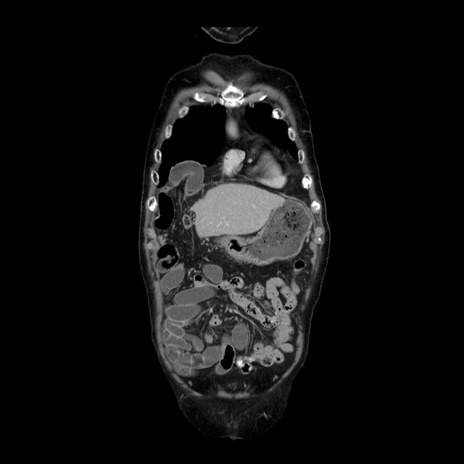

症例21(冠状断像)

【症例】70歳代男性

【主訴】腹痛

【現病歴】肝硬変・肝細胞癌にてかかりつけの方。約9時間前に食後より腹痛出現。症状が徐々に増悪し、嘔吐出現したため来院。

【既往歴】肝硬変、肝細胞癌(RFA、TACE後)

【身体所見】意識清明、表情苦悶様、BT 36℃、BP 129/78mmHg、P 88bpm、SpO2 97%(RA)、右上腹部から心窩部にかけて圧痛あり、反跳痛なし、筋性防御あり。

【データ】WBC 5800、CRP 0.16